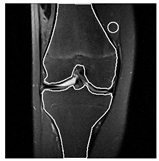

| Edema | 21 | Edema | Non-edema | ![]() | ![]() |

| Edema | 21 | Non-edema | Edema | ![]() | ![]() |

| Non-edema | 2 | Non-edema | Edema | ![]() | ![]() |

| Non-edema | 5 | Non-edema | Edema | ![]() | ![]() |

| Non-edema | 20 | Non-edema | Edema | ![]() | ![]() |

| Non-edema | 30 | Non-edema | Edema | ![]() | ![]() |